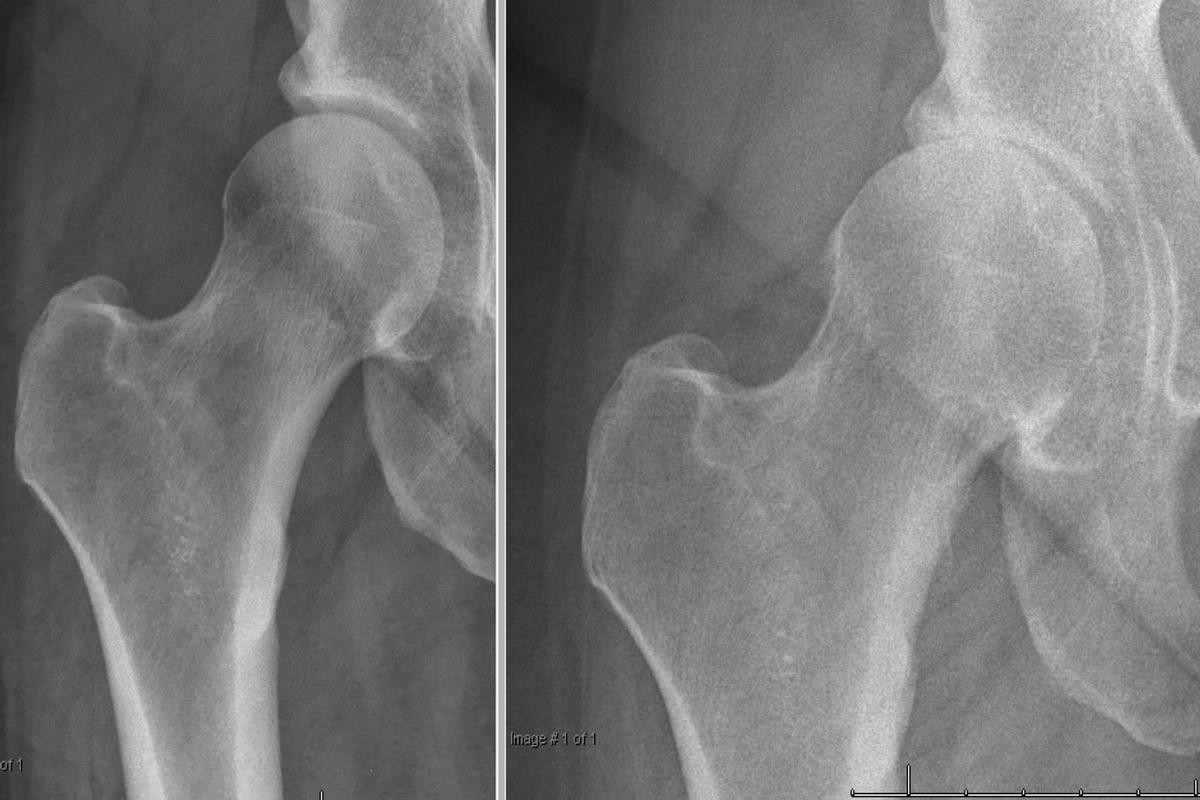

Ακτινογραφία ισχίου αποτελεί την εξέταση πρώτης γραμμής και αναδεικνύει:

Στένωση μεσάρθριου διαστήματος

Οστεόφυτα

Υποχόνδρια σκλήρυνση

Παραμόρφωση κεφαλής